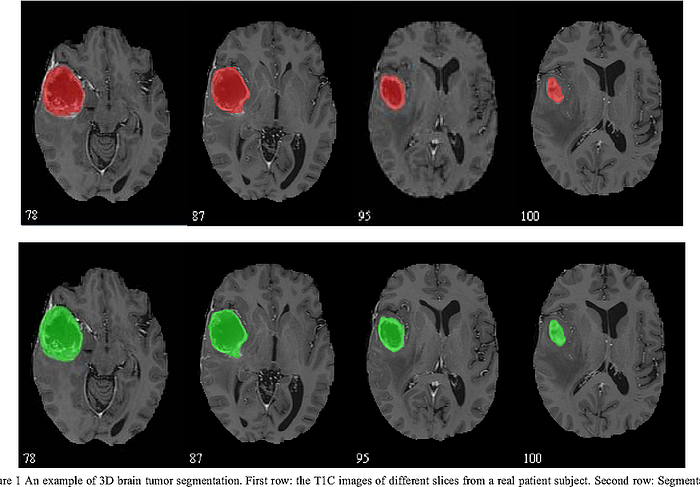

假设一位医学专业人士正在检查脑部扫描图像,试图找到潜在的癌性病变。这就是图像分割发挥作用的地方。分割过程用于识别图像中的不同组织和结构,在区分癌细胞和其他正常组织方面发挥着重要作用。

例如,在下面的脑部扫描图像中,分割已经识别出癌性肿瘤并以不同的颜色显示。